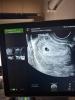

Сходили на УЗИ с мужем. Сердцебиения еще не услышали, эмбриона тоже нет.

ПЯ - 10.5 мм

ЖМ - 3.1 мм

@holaihateu как мне узистка еще в прошлую Б объясняла, желточный мешочек как кольцо с бриллиантиком) вот слева на нем точку видите? Это ваш бриллиантик)) потом он будет расти, станет белым и мерцать))

@regishkase7en, я тоже фотографии в интернете посмотрела вчера на маленьком сроке и тоже ассоциация была кольца с бриллиантом) у нас видео записано, там видно лучше, что эмбрион есть. Просто крошечный еще ☺️

Видно уже где эмбриончик будет😊